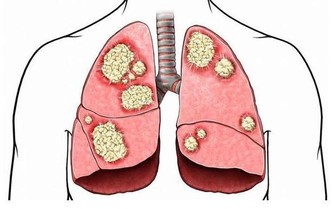

3.吸煙

吸煙的壞處不用多提,除了肺癌、糖尿病等,它還會加劇慢性頸椎痛。

吸煙會減少背部和頸部骨頭中的水分,從而加速這些部位的退化,嚴重可導致椎間盤突出,影響脊椎正常功能。另外,吸煙還會使血管硬化,使得輸送至脊椎和骨頭的氧氣量減少。